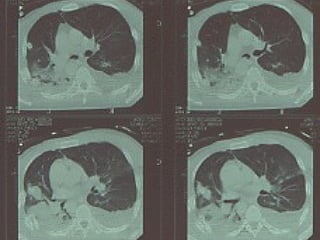

Tc pre op